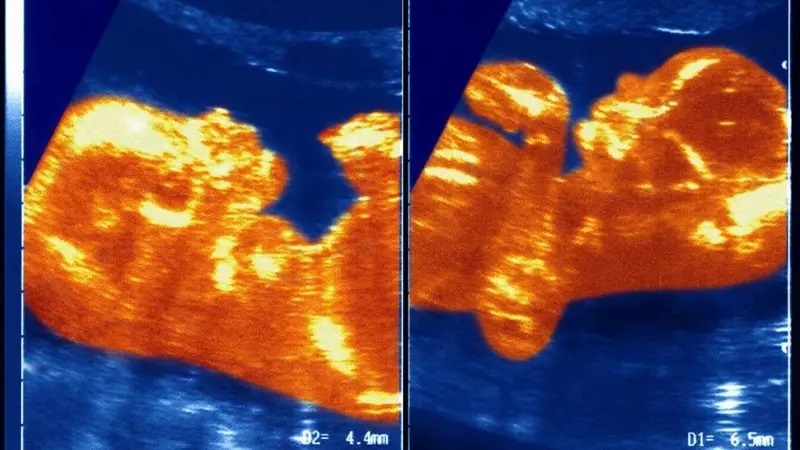

محققان گمان میکنند که در دوران جنینی، جفت آنا پائولا و برادر دوقلویش به نوعی با هم تماس داشتهاند و این امر باعث شکلگیری پیوندی از رگهای خونی شده که خون را از پسر به دختر منتقل میکرده است.

پروفسور ماسیل توضیح میدهد: «فرایند انتقال خونی وجود داشته که ما آن را انتقال جنین به جنین مینامیم. در مقطعی، وریدها و شریانهای هر دو در بند ناف در هم تنیده شدند و برادرش همه مواد خونیاش را به آنا پائولا منتقل کرد.»

سلولهای خونی برادرش احتمال میرود دوباره مغز استخوان آنا پائولا را اشغال کرده باشند و باعث شده باشند که مغز استخوان او خونی با کروموزومهای ایکس وای تولید کند، در حالی که بقیه بدنش همچنان دارای کروموزومهای ایکس ایکس باقی مانده است.